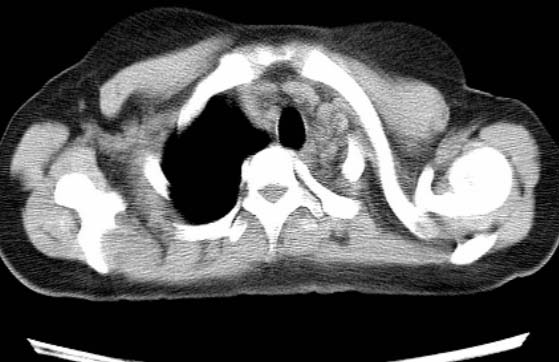

标题: CT25648:求教:是肺发育不全还是结核?

女  20岁。一月前咳血,诊“肺结核”抗痨治疗一月后,咳血停止,现复查。病人精神好。前后ct片对比未见明显变化。既往体检“正常”

1)考虑左肺结核并肺不张、支气管扩张。2)纵隔疝。

考虑左肺结核,左肺毁损,纵膈左偏,既往体检正常不可靠,tb一个月也不会这个样子的,有钙化,应该病程较长,冰冻三尺非一日之寒!